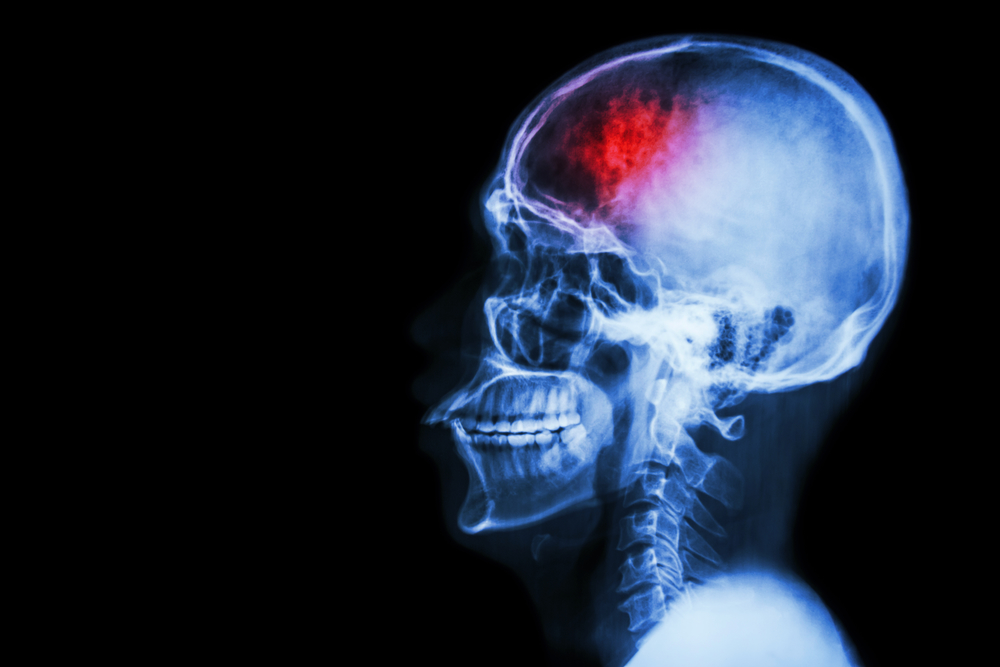

Em primeira instância, é importante sabermos do que se trata, afinal, um derrame.

Ele ocorre quando o seu cérebro não recebe a quantidade de nutrientes e de oxigênio que ele deveria receber normalmente.

E o derrame hemorrágico, provocado por um sangramento.

– Derrame hemorrágico, provocado por um sangramento.